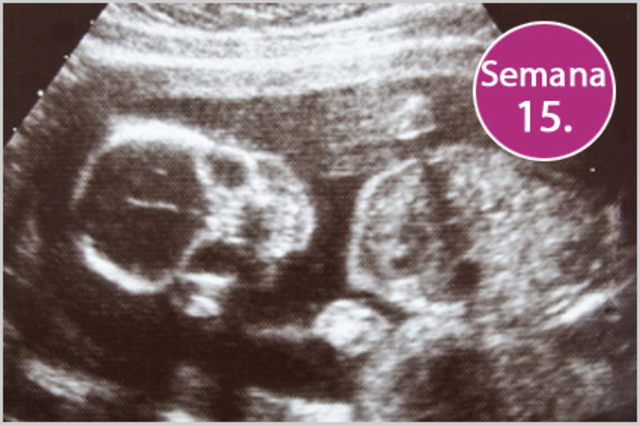

• Semana 15

Semana 15

-La piel del feto es casi transparente.

-El feto posee reflejo de succión.